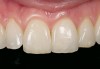

Mechanical properties are low, with flexural strength usually from 60 MPa to 70 MPa. Thus, they tend to be employed as veneer materials for metal or ceramic substructures, as well as for veneers, using either a refractory die technique or platinum foil. The microstructure of a glass is shown in Figure 1. This is an electron micrograph of an acid-etched glass surface. The holes indicate a second glass, which was removed by the acid. The veneer restoration uses a glassy porcelain (Figure 2A and Figure 2B).

The original materials had a fairly random size and distribution of leucite crystals with the average particle size of approximately several hundred microns. This random distribution and large particle size contributed to the material’s low fracture resistance and abrasive properties relative to enamel.8 Newer generations of materials have been developed with much finer leucite crystals (10 µm to 20 µm) and very even particle distribution throughout the glass. These materials are less abrasive and have much higher flexural strengths.9 In Figure 3, an electron micrograph of a typical feldspathic porcelain reveals a glass matrix surrounding leucite crystals. These materials are most commonly used as veneer porcelains for metal-ceramic restorations (Figure 4).

Vitablocs are fabricated using fine-grain powders, producing a nearly pore-free ceramic with fine crystals. This was the first material specifically produced for the CEREC system and has an excellent history of clinical success for inlays, onlays, and anterior and posterior crowns.36 Sirona CEREC Blocs are fabricated from the same powders. The restoration may be characterized with external stains, or porcelain may also be added to produce a layered effect (17A and Figure 17B). These blocks are available as monochromatic, polychromatic with stacked shades as in a layer cake, and in a form replicating the hand-fabricated crowns in which an enamel porcelain is layered on top of dentin porcelain.